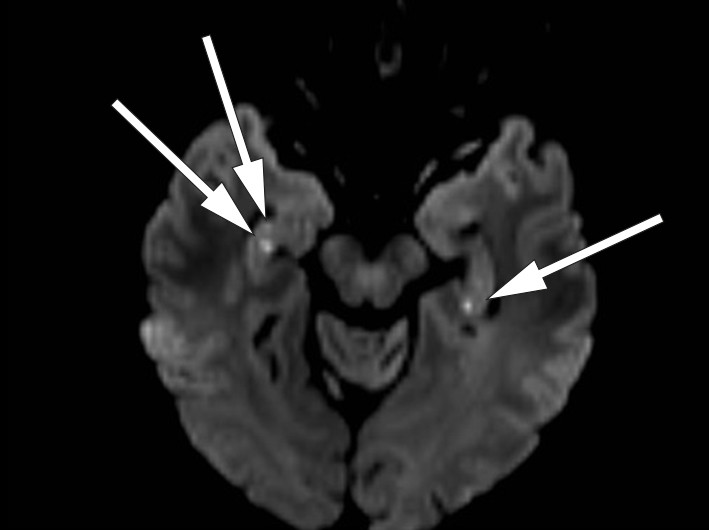

Vår pasient hadde normalt EEG og normale blodprøver. MR caput på 3 Tesla-maskin viste normale forhold på ordinær diffusjonsvektet snittserie med 4 mm tykke snitt. På diffusjonsvektet snittserie med 2 mm snitt ble det funnet to punktformede diffusjonsavvik på hver side av samme dato svarende til hippocampus (bilde 1 og 2).

MR-funnene er typiske for transitorisk global amnesi. Da slike lesjoner er såpass små, lar de seg best påvise ved 3 Tesla MR-maskin med en snittprotokoll som omfatter tynne (2 – 3 mm), tette (snittavstand 2 – 3 mm) diffusjonsvektede snitt, der snittserien anlegges parallelt med hippocampusstrukturenes lengdeakse. Lesjonene lar seg lettest avdekke 48 – 72 timer etter symptomstart. Lesjonene er ikke spesifikke for transitorisk global amnesi, og påvisning av slike MR-forandringer kan føre til en feilaktig hjerneinfarktdiagnose. Det kliniske bildet er avgjørende for å skille tilstanden fra isolerte hippocampusinfarkt (3, 4).

Vår pasient hadde et klinisk bilde vel forenlig med transitorisk global amnesi, med ledsagende typiske lesjoner på MR-bildet. MR-bilder seks uker etter symptomdebut viste komplett tilbakegang av aktuelle lesjoner.